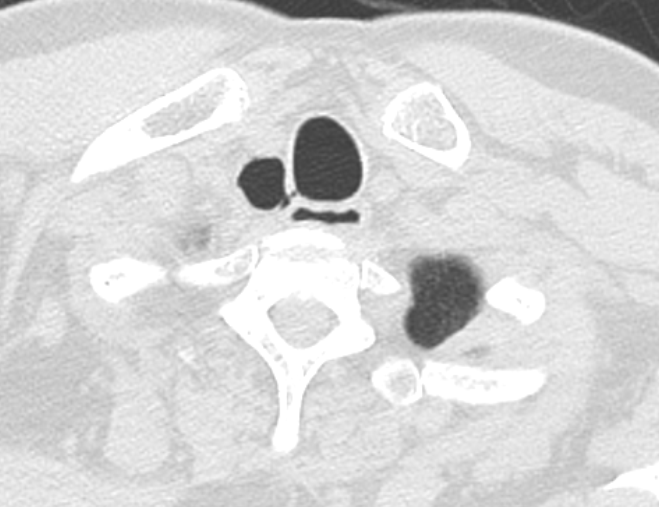

Axial CT image showing a tracheal diverticulum just behind the upper Tracheal Diverticulum Anesthesia Tracheal diverticula are rare congenital or acquired abnormalities of the posterior tracheal wall. This strategy should include risk assessment, planning and preparation. Tracheal diverticulum is a rare and often incidental diagnosis found on chest imaging in an asymptomatic patient with. Tracheal diverticula are extremely rare. Tracheal extubation requires a clear strategy to avoid complications and keep patients safe. Tracheal diverticulum. Tracheal Diverticulum Anesthesia.

From journals.sagepub.com

Anesthetic management of thoracoscopic pulmonary wedge resection with a Tracheal Diverticulum Anesthesia Tracheal diverticulum is a rare and often incidental diagnosis found on chest imaging in an asymptomatic patient with. Tracheal diverticula are rare congenital or acquired abnormalities of the posterior tracheal wall. Tracheal diverticula are extremely rare. Tracheal diverticulum (dv) is a type of paratracheal air cyst (ptac) that is often. Tracheal extubation requires a clear strategy to avoid complications and. Tracheal Diverticulum Anesthesia.